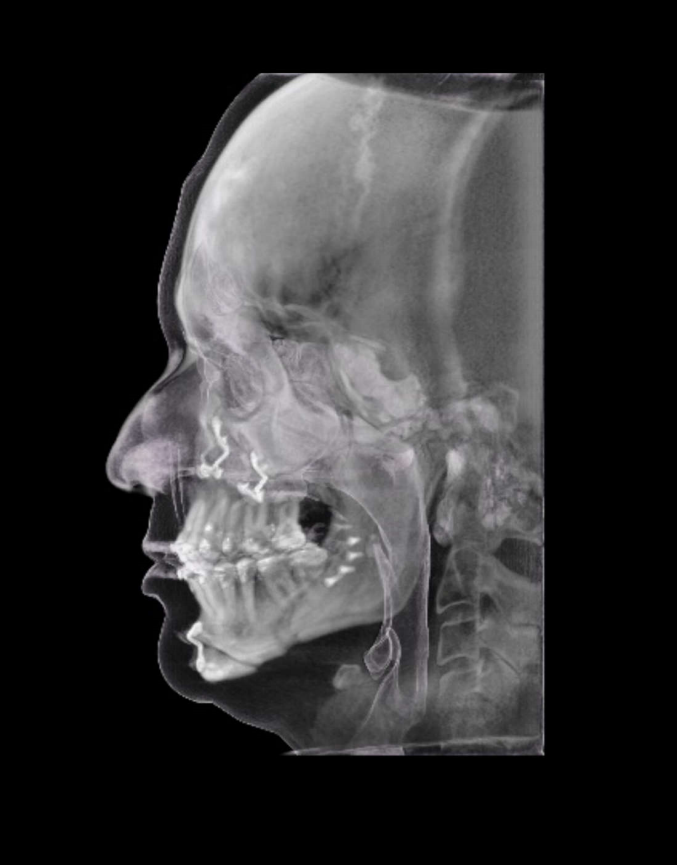

TC de face (do Hióide à Glabela), reconstrução 3D do tecido ósseo, radiografia panorâmica, telerradiografia lateral com traçado, cortes transversais e axial de maxila e mandíbula e arquivo DICOM- entregue em pasta de Pvc.

TC de face (do Hióide à Glabela), reconstrução 3D do tecido ósseo, radiografia panorâmica, telerradiografia lateral e frontal com traçado, cortes transversais e axial de maxila/mandíbula e arquivo DICOM – entregue em pasta de Pvc.

TC de face (do Hióide à Glabela), reconstruções 3D do tecido mole/ósseo/vias aéreas, radiografia panorâmica, telerradiografia lateral e frontal com traçado, cortes transversais e axial de maxila/mandíbula, ATM e arquivo DICOM – entregue em pasta e caixa de Pvc.